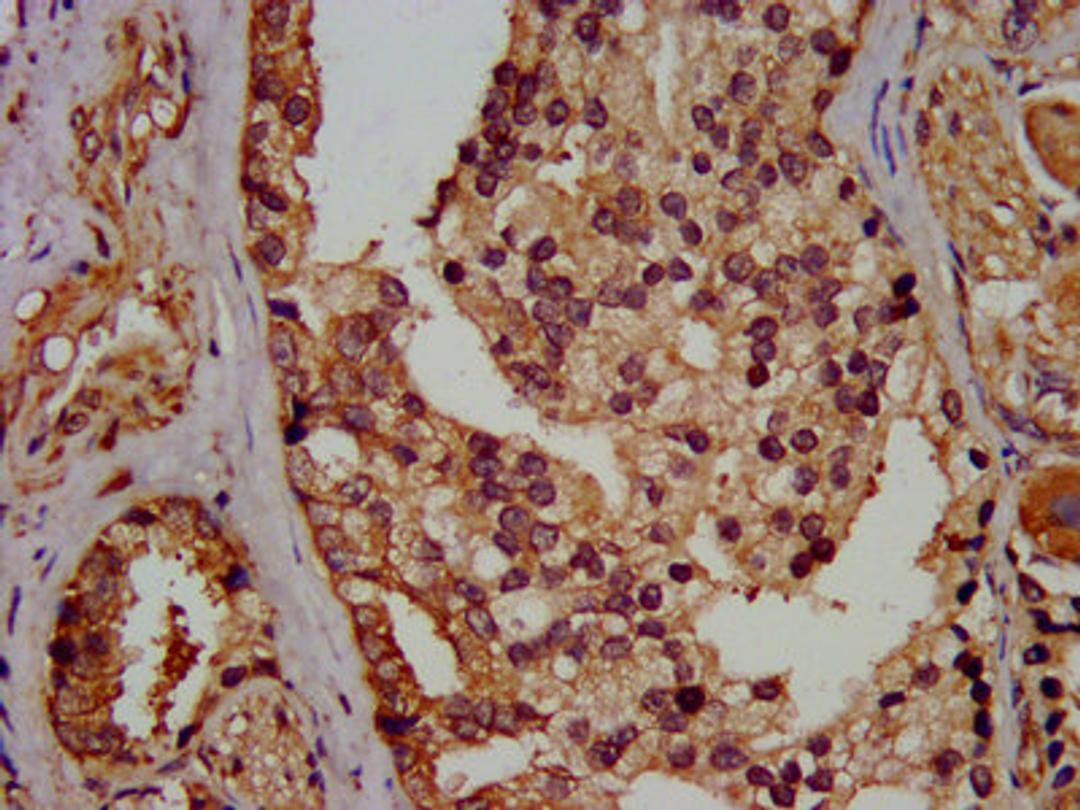

IHC image of CSB-PA03099A0Rb diluted at 1:400 and staining in paraffin-embedded human prostate cancer performed on a Leica BondTM system. After dewaxing and hydration, antigen retrieval was mediated by high pressure in a citrate buffer (pH 6.0). Section was blocked with 10% normal goat serum 30min at RT. Then primary antibody (1% BSA) was incubated at 4°C overnight. The primary is detected by a biotinylated secondary antibody and visualized using an HRP conjugated SP system.